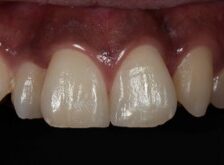

ダイレクトボンディングなどの

審美治療も高精度に対応